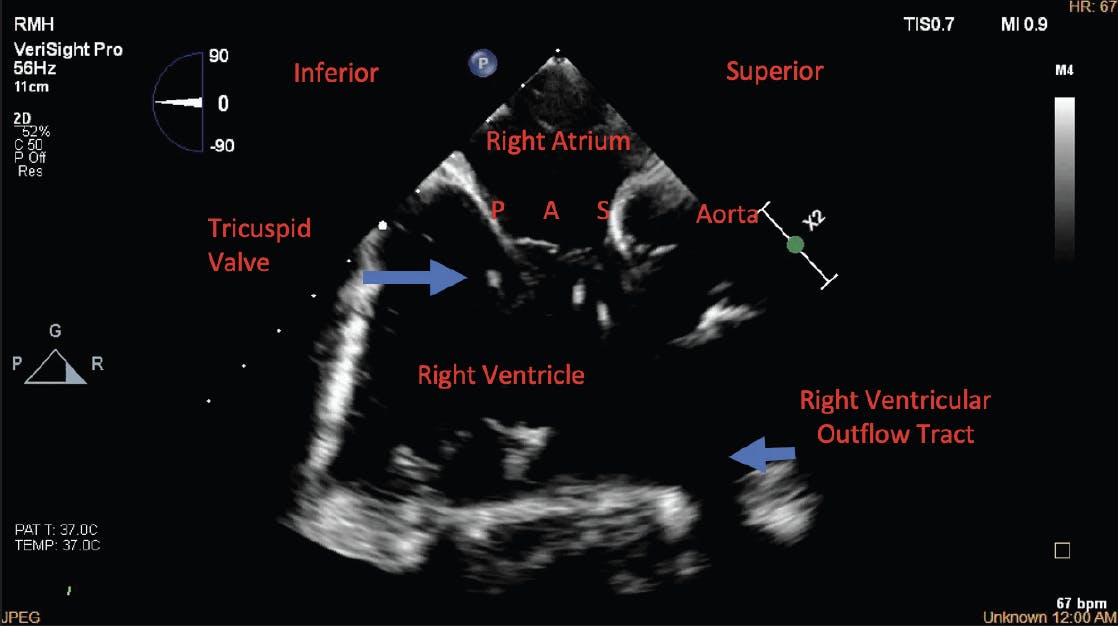

Figure 4. 2D ICE view showing all three tricuspid leaflets from the home view. P, posterior leaflet; A, anterior leaflet; S, septal leaflet.

The initial 3D ICE imaging for the TV is the home view position in the right atrium (RA) with and without color to identify all three TV leaflets and origination of the TR jet (Figure 4). Biplane images are obtained to determine the area of maximum regurgitation and full anatomic assessment, including an RV inflow/outflow view (Figure 5). A multiplane reconstruction (MPR) view is obtained by placing the crosshair markers across the TV, creating a 3D en-face view of the TV in real time. Ideally, the aortic valve is placed at the nine o’clock position to help identify all leaflets in a consistent manner, according to this anterior landmark. From this view, anterior, posterior, and septal leaflets are identified (Figure 6). The TV often has more than three leaflets. The steerable guide catheter (SGC) is identified in the RA, and the clip delivery system (CDS; Abbott) is viewed while exiting the SGC. The CDS is steered from the septal side of the RA toward the TV, and the clip is positioned above of the TV regurgitant jet.